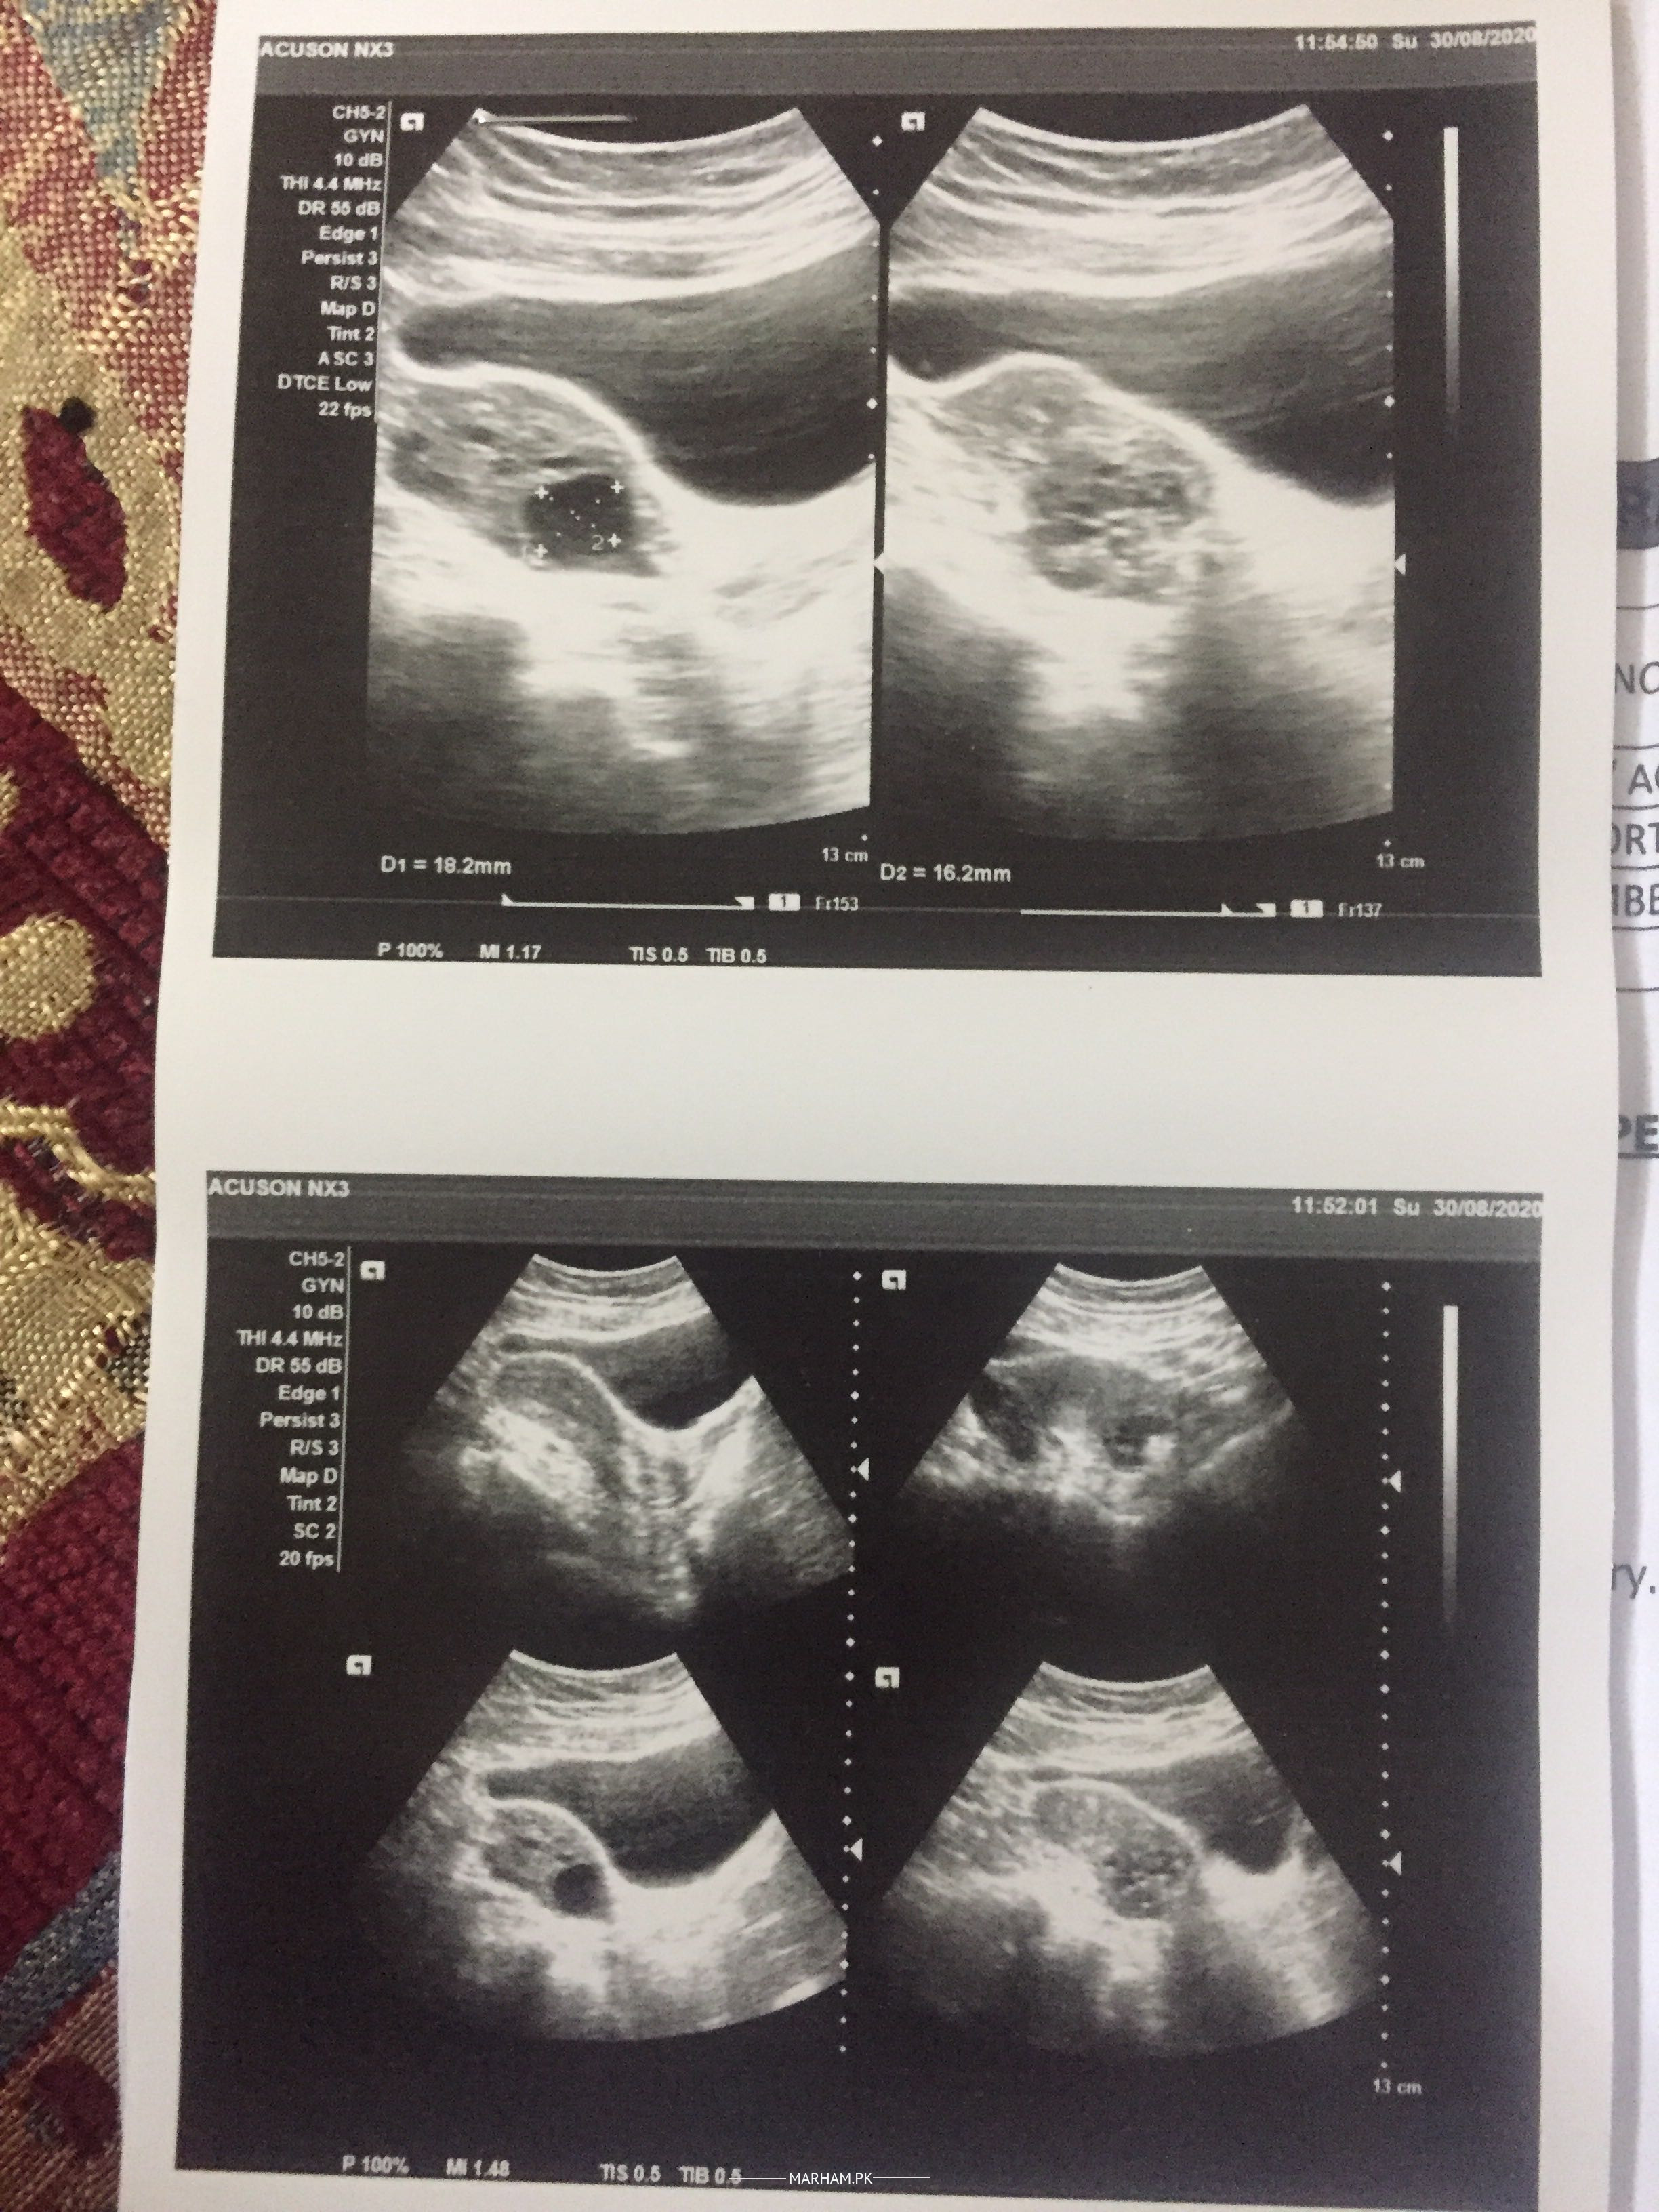

Mjha ya pOchna ha ma 2 years sa try kr rae baby k liya ... phla mjha cyst ka issue tha but kafiii mahinO sa wo issue khatam hO gaya ha ... Then ma na pregnancy treatment krwayaaaa lakin still conceive nae hO rha .. sara test thk ha mra b aur mra husband k b .. abhi august ma 19 ko perioDs ay mjhaaa aur doctor na mjha 12th day pa pelvic scan ka bola aur report blkul thk ai ... ma attach kr rae hn .. par abhi september 18 mjha perioDs agay conceive nae hOa .. Q nae ho pa rha conceive jb sb thk ha tO plzzz guide me .. i’m very upset